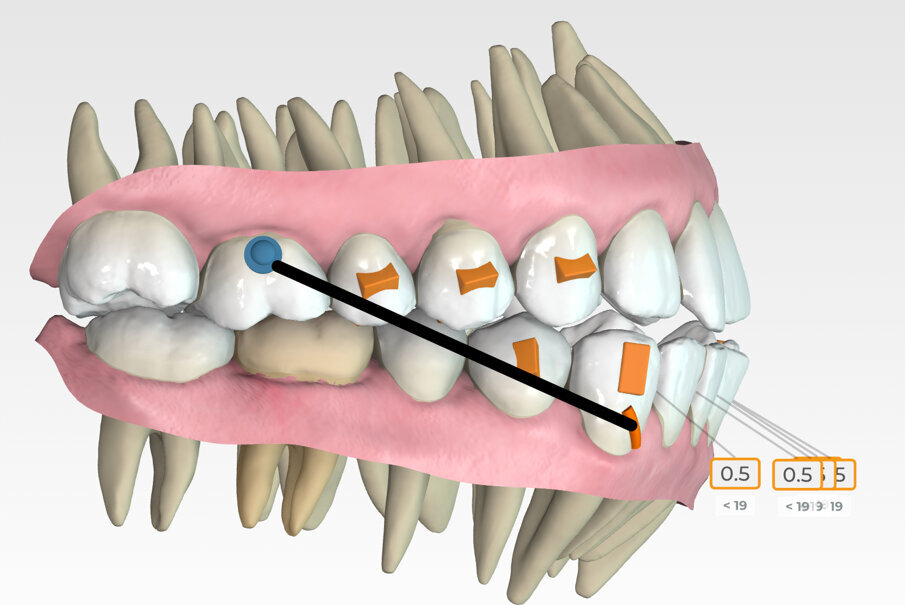

Lower arch expansion and interproximal reduction of 0.5 mm were prescribed on all of the lower incisors from mesial of canine to mesial of canine before the 19th aligner. (Fig. 13) IPR would allow retraction to assist the Class III elastic correction of the negative overjet. Additionally, since counterclockwise autorotation of the mandible would project the lower incisors anteriorly, retraction would also assist in mitigating this effect.

Retraction and uprighting of the lower incisors would also achieve relative extrusion, further assisting in the closure of the anterior open bite. (Figs. 14,15)